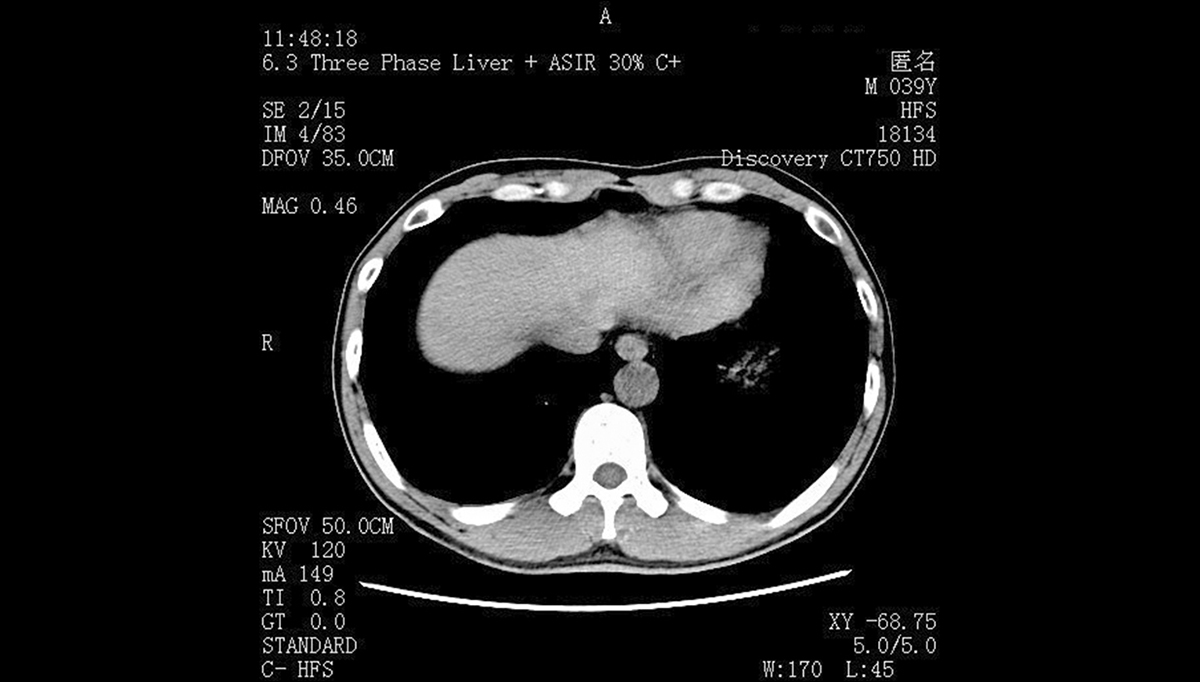

第一,色彩与灰阶精准度不同。医用显示器需严格遵循DICOM标准,支持1024级及以上灰阶显示,能清晰呈现CT、MRI影像中的细微病灶(如微小结节、血管纹理),色彩还原误差控制在极小范围。而民用显示器侧重视觉体验,灰阶多为256级,色彩可人为调校,无需精准匹配医学影像需求。